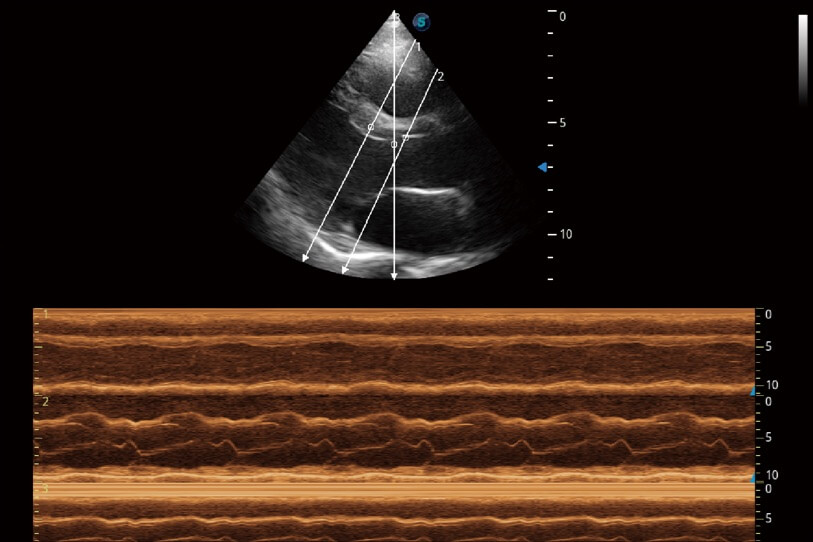

通過360度任意調(diào)節(jié)3條M型取樣線,在同一心動周期上觀察心臟不同位置的運動曲線,得到準確的心功能測量數(shù)據(jù),有效評估心肌運動及左心室功能。